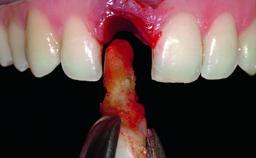

A 36-year-old male patient with a compromised maxillary central incisor was referred by his general dentist for consultation. The patient’s chief complaints were the gradual debonding of a temporary crown on the right central incisor and unsatisfactory esthetics due to an increasing diastema between the right central and lateral incisors. The patient reported a traumatic event some years previously, when a crown had been placed after root-canal treatment. The referring dentist wanted to provide a new crown restoration, but was concerned about the condition of the residual root. Anamnesis was negative for any other dental or periodontal pathology in the remaining dentition. The patient reported taking no medications: He was a smoker (10 to 15 cigs/day) and had realistic esthetic expectations.

Bone Augmentation Horizontal|Simultaneous|Staged

Augmentation Materials Xenogenous|Membrane

Soft Tissue Grafting Simultaneous

Bone Volume Deficient horizontally, requiring prior grafting